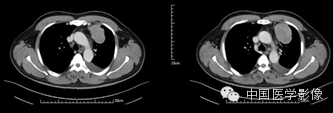

病例1【病史】

患者男,50岁。

患者因“突发胸痛4余天”入院。患者无发热、盗汗,无声音嘶哑,无咳痰,无面部及双下肢肿胀。门诊以“左前上纵膈肿瘤”收入院。患者自发病以来,饮食睡眠可,大小便正常,体重较前无明显减轻。既往高血压病史1年,否认其他传染病史。

专科查体:胸廓对称,双侧呼吸动度均等,胸壁无明显压痛及肿块,双侧语颤正常,双肺叩清音,左下肺呼吸音低,右肺呼吸音可,双肺未闻及干湿啰音。

入院诊断:左前上纵膈肿瘤:畸胎瘤?

【影像资料】

平扫

动脉期

静脉期

延迟期

【病理结果】

孤立性纤维性肿瘤